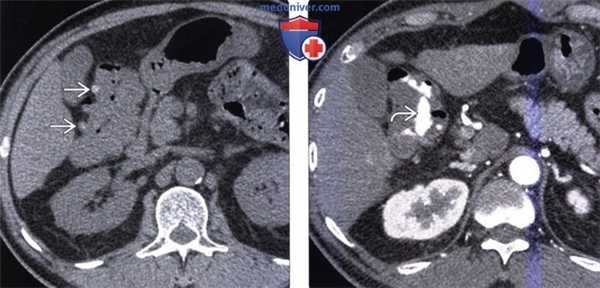

(Слева) На аксиальной КТ без контрастного усиления у мужчины 75 лет с ректальным кровотечением (гематокезией) визуализируется дивертикул правых отделов ободочной кишки.

(Справа) На КТ с контрастным усилением в артериальную фазу контрастирования у этого же пациента определяется активная экстравазация крови в просвет восходящей ободочной кишки, что является диагностическим признаком острого и тяжелого кровотечения, обусловленного дивертикулезом.

(Слева) На корональной КТ в этом же случае определяется накопление контрастированной крови в просвете ободочной кишки. Также визуализируется правосторонний дивертикул.

(Справа) Рентгенограмма (ангиограмма верхней брыжеечной артерии) позволяет подтвердить активное кровотечение из ветви правой ободочной артерии в просвет ободочной кишки. Дивертикулез - относительно частая причина ректального кровотечения.